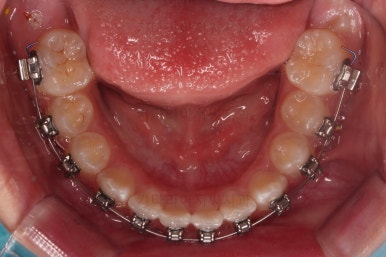

마무리를 해줍니다.

앞니 각도가 매우 좋아졌고요.(옥니 개선) 위아래 앞니가 덮는 정도도 개선이 되었어요.(과개교합, 딥바이트)

엉성했던 어금니 맞물림도 매우 좋아졌어요.(앵글씨 2급 부정교합 개선)

전후사진을 비교해 볼게요.

협조도가 요구되는 장치를 잘 못끼는 바람에 중간에 우여곡절이 있었고, 힘든 과정이 있었지만 비교적 부산교정병원 만족스러운 치료를 할 수 있었어요.

이상 일정부분만 성장교정과 치아교정을 통해 옥니, 과개교합, 앵글씨 2급 부정교합을 치료한 부산교정병원 치료사례였습니다.